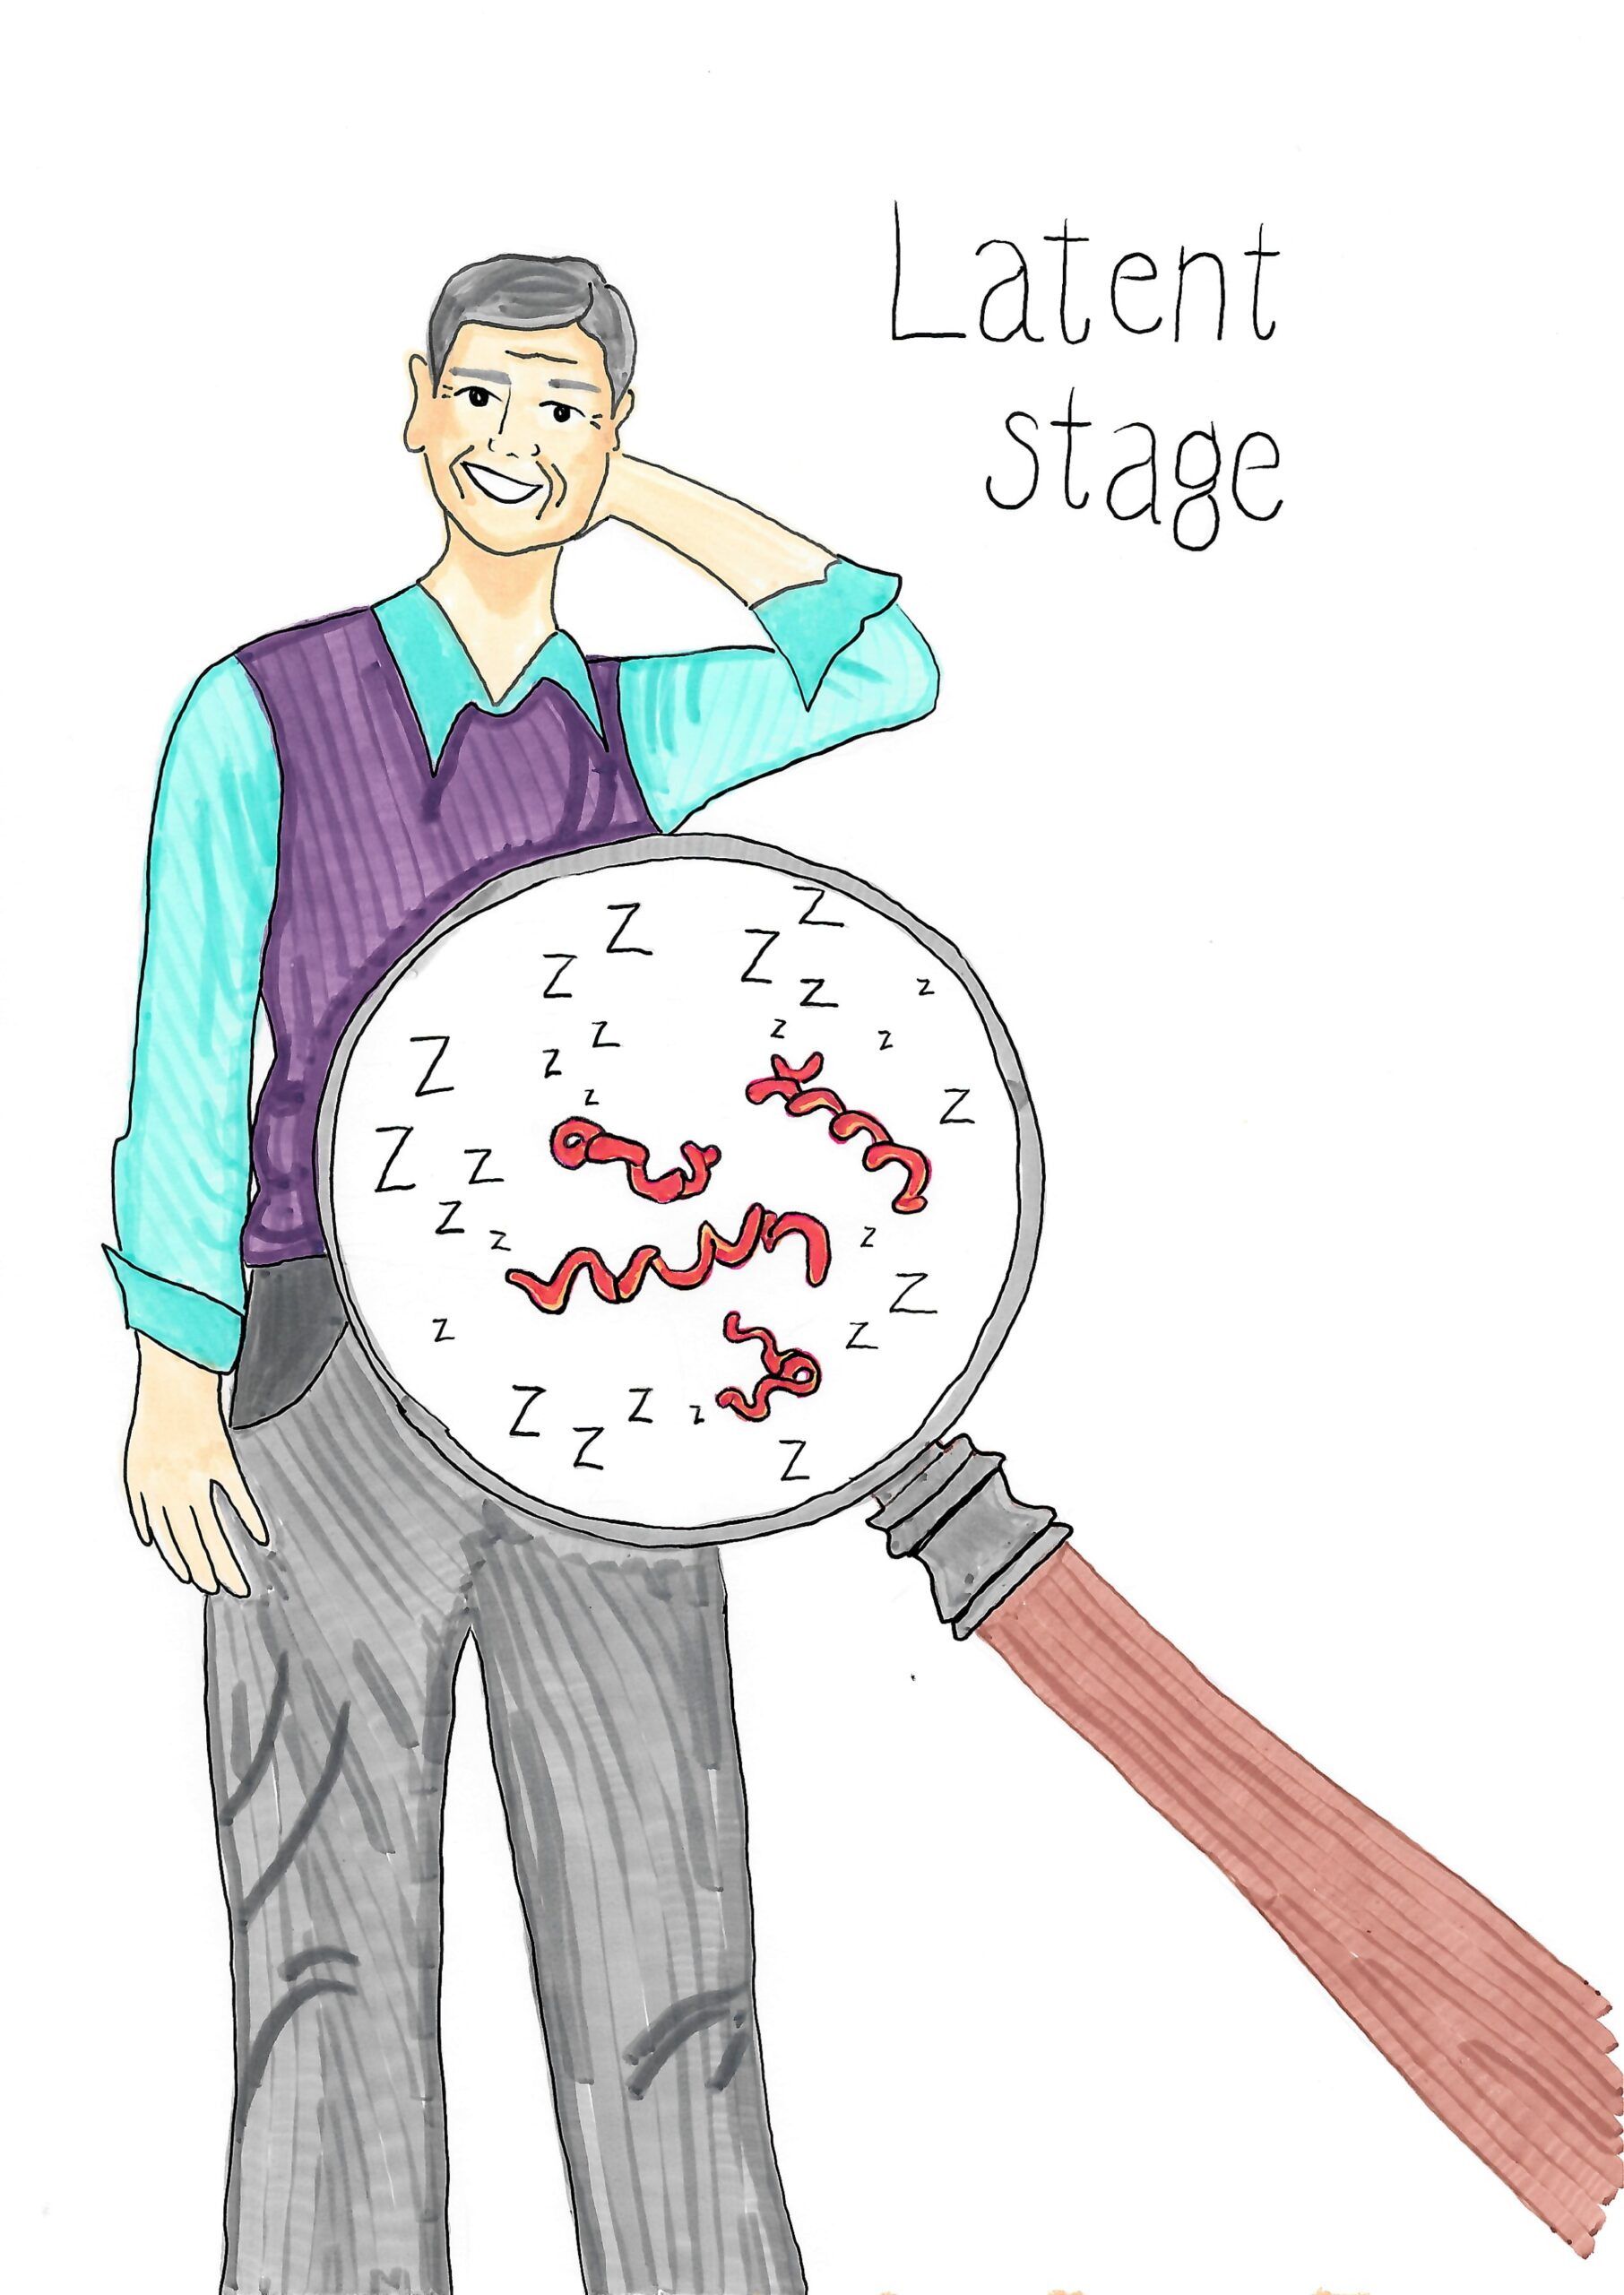

Latent Stage Syphilis

Latent Stage Syphilis

Possible during Stage Three Syphilis, and not everyone will develop this. No symptoms.

If left untreated, Secondary Syphilis may progress to the latent (hidden) phase. Not everyone who has Syphilis will go through this stage. For those who do, there won’t be any symptoms, maybe for years. In some cases, symptoms will never return. But the infection isn’t gone; the bacteria remain inactive in the body and will still show up in a test.

Transmission risks during the latent phase are much lower than during other stages. Foetal transmission can occur during this time.

Some latent cases may progress to the tertiary stage of the disease.

Not all people with latent Syphilis will develop Tertiary Syphilis.